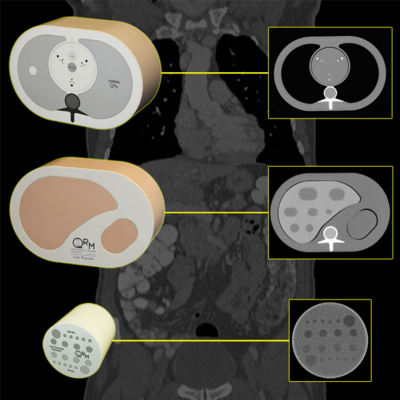

Phantoms for CT and DXA to measure the BMD (Bone Mineral Density)

Phantoms for Micro-CT systems to calibrate bone densities and other materials as iodine, and to test low contrast capabilities of the scanner.